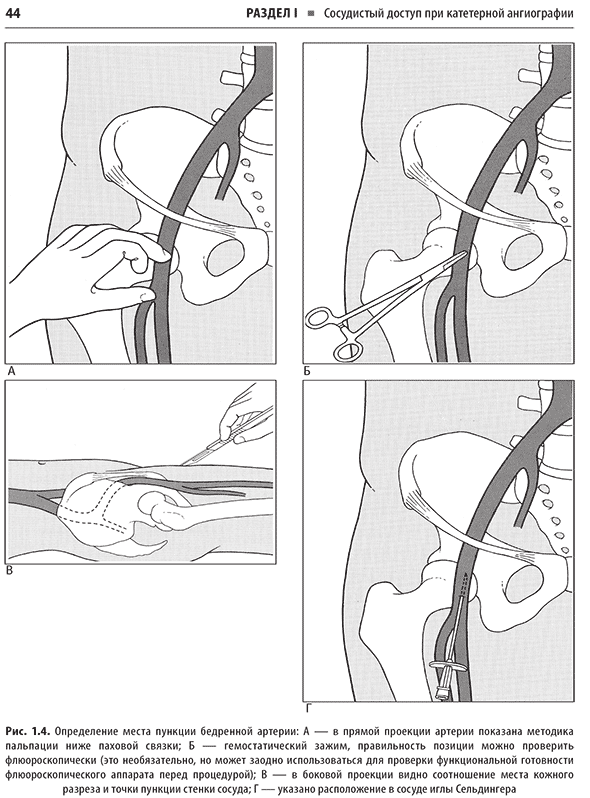

Справочник охватывает все ключевые аспекты, необходимые для успешной практики: показания, противопоказания, подготовку, технику выполнения, ведение пациентов после процедуры, а также профилактику и лечение возможных осложнений. В нем уделено особое внимание протоколам и оборудованию, что позволяет уверенно выполнять сложные манипуляции. Дана информация о сестринском деле, лекарственных препаратах и дозировках, что поможет обеспечить безопасность и комфорт пациентов. Простые линейные рисунки иллюстрируют анатомию и ход процедур, облегчая понимание сложных тем. Представлены сведения о катетерной ангиографии, трансартериальных и трансвенозных процедурах, а также о ведении пациентов во время процедуры.

Примеры страниц из книги "Справочник по интервенционным радиологическим процедурам" - К. Кандарпы, Л. Мачан, Дж.Д. Дюрам